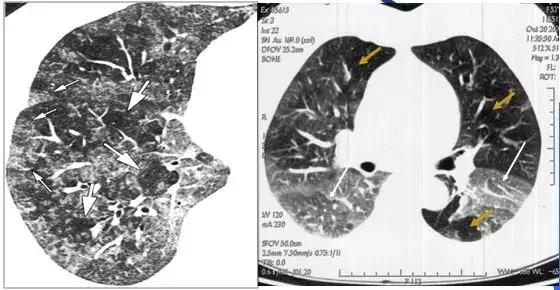

CT征象一:树芽征

由终末细支气管和肺泡腔内病变形成的小结节影与分支细线影构成的酷似春天的树枝发芽状,称“树芽征”(tree-in-bud)

CT表现:多在肺外围支气管末梢呈2-4mm大小结节与树枝状的高密度影。

意义:多表明有小气道病变如:细支气管炎症、弥漫泛发性细支气管炎及肺结核病灶或播散等

末梢细支气管扩张形成粘液栓——酷似“树芽征”

末梢细支气管与肺泡结核灶及播散——酷似“树芽征”

末梢细支气管感染——HRCT与HE病理切片图显示“树芽征”

“树芽征”:活动性肺结核支气管播散;泛细支气管炎